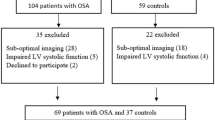

A total of 80 patients with first OSAS were initially evaluated. Nine patients were excluded: 5 (8%) patients did not have sufficient image quality for tracking of RV walls. Another 4 (7%) patients refused to enroll in the study. Thus, 71 patients were enrolled in the present study. Mean age was 48.0 ± 7.8 years, and 52 patients were males. Thirty-one patients matched to age and sex were control group.